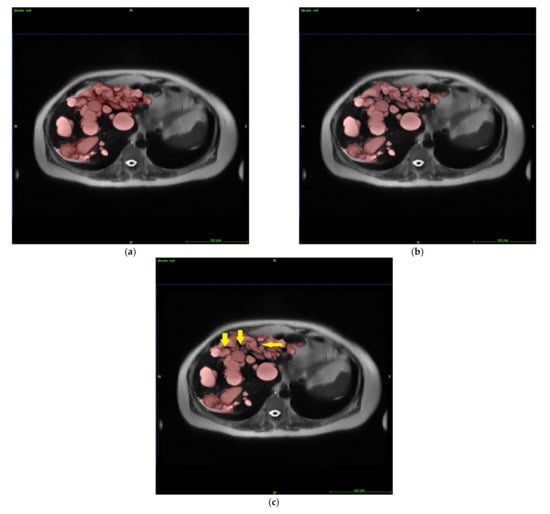

Figure 4.

Liver cyst segmentation by manual GT (a), automated LS (b), and IRIS (c). The voxels in the space between neighboring cysts (arrows in (c)) were easily included in the manual GT, contributing to the observed segmentation errors. GT = ground truth segmentation, LS = automatic level set segmentation, and IRIS = intelligent rapid interactive segmentation.

The discrepancies between manual GT, automated LS, and IRIS segmentations were reviewed and were largely caused by voxels at cyst edges and/or in spaces between neighboring cysts that were easily included in manual segmentation, as illustrated by arrows in Figure 4 and also subtly noticeable on Figure 1.

It should be noted that manual segmentation is not a perfect ground truth. Small cysts can be missed on manual segmentation because it is so tedious and tiring, as exemplified in Figure 1. The largest normalized volume error (38.7%) occurred in a case with a small liver cyst volume (13 mL by manual segmentation and 8 mL by IRIS) and was largely caused by discrepancies at border voxels. The large absolute volume error (35.9 mL) occurred in a case with a large liver cyst volume (1538 mL by manual and 1411 mL by IRIS) and was largely caused by voxels in spaces between neighboring cysts (Figure 4). We feel that IRIS can provide a more consistent border definition for cysts and, therefore, a better ground truth.